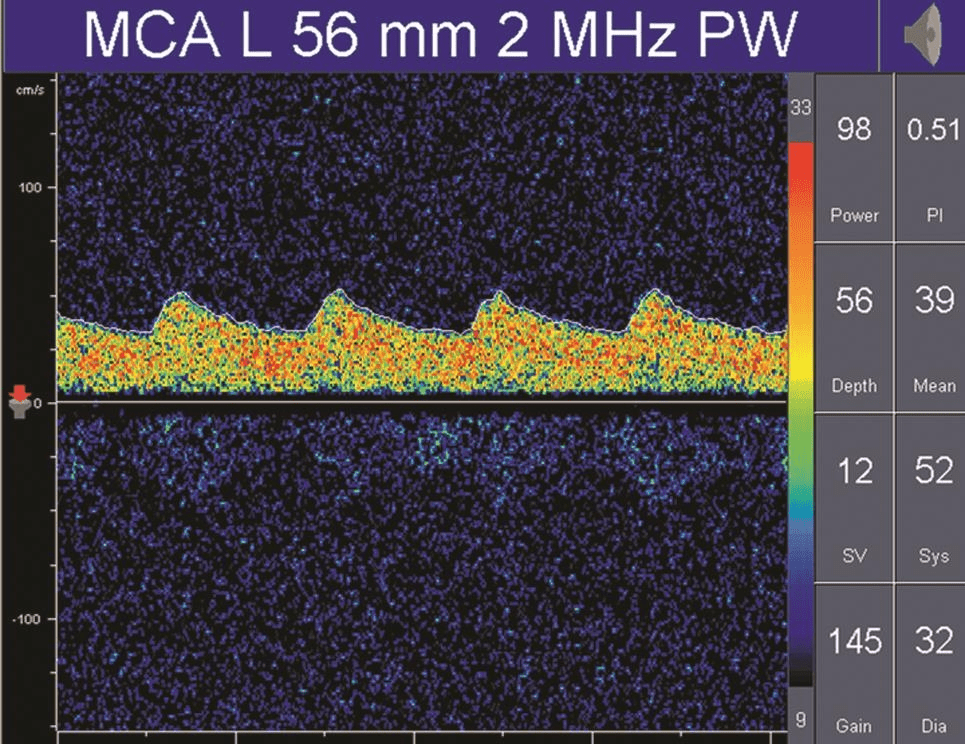

搏動指數(shù)(pulsatility index,PI)和阻力指數(shù)(resistant index,RI)是描述頻譜形態(tài)的參數(shù),通常是由血流速度計算出來,計算公式為:PI=(Vs-Vd) /Vm,RI=(Vs-Vd) /Vs。

PI值主要受收縮期和舒張期血流速度差的影響,差值越大,PI值越大;差值越小,PI值也越小。

因此,PI值可以反映血管內(nèi)血流壓力灌注情況或遠端血管的阻力大小。

正常情況下顱內(nèi)血管的血流頻譜為相對低搏動性波形(PI值為0.55~1.05),而外周血管(顱外頸動脈或肢體血管)為相對高搏動性或高阻力波形(PI值通常大于1.05),顱內(nèi)正常搏動指數(shù)和阻力指數(shù)的頻譜(詳情見下圖)。

在病理情況下,低阻力頻譜可見于動靜脈畸形供血動脈、大動脈嚴重狹窄或閉塞后遠端灌注明顯不足的血管內(nèi)血流及開放的側(cè)支循環(huán)(詳情見下圖);

TCD多普勒TCD低阻力血流頻譜

可見,除血流速度和血流方向之外,PI值是分析TCD血流頻譜的另一個非常重要的參數(shù)。